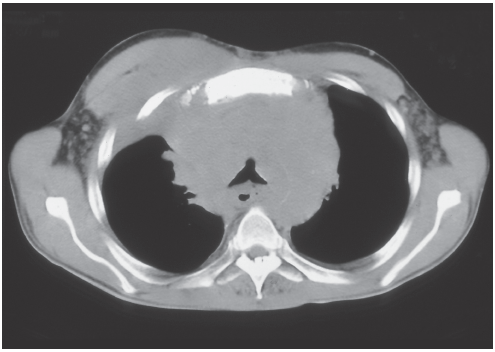

A CT scan of the thorax showed an anterior mediastinal mass surrounding and compressing the trachea (Figure 2). Results of a mediastinoscopic biopsy of the lesion were consistent with a non-Hodgkin lymphoma.

Figure 2 – This CT scan of the patient’s thorax shows an anterior mediastinal

mass surrounding and compressing the trachea.